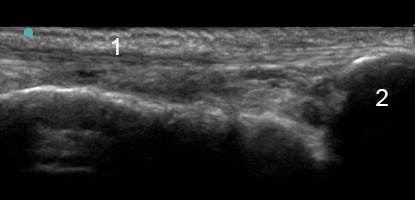

1. Tendon court fibulaire

2. S'insère sur la base du 5e métatarsien